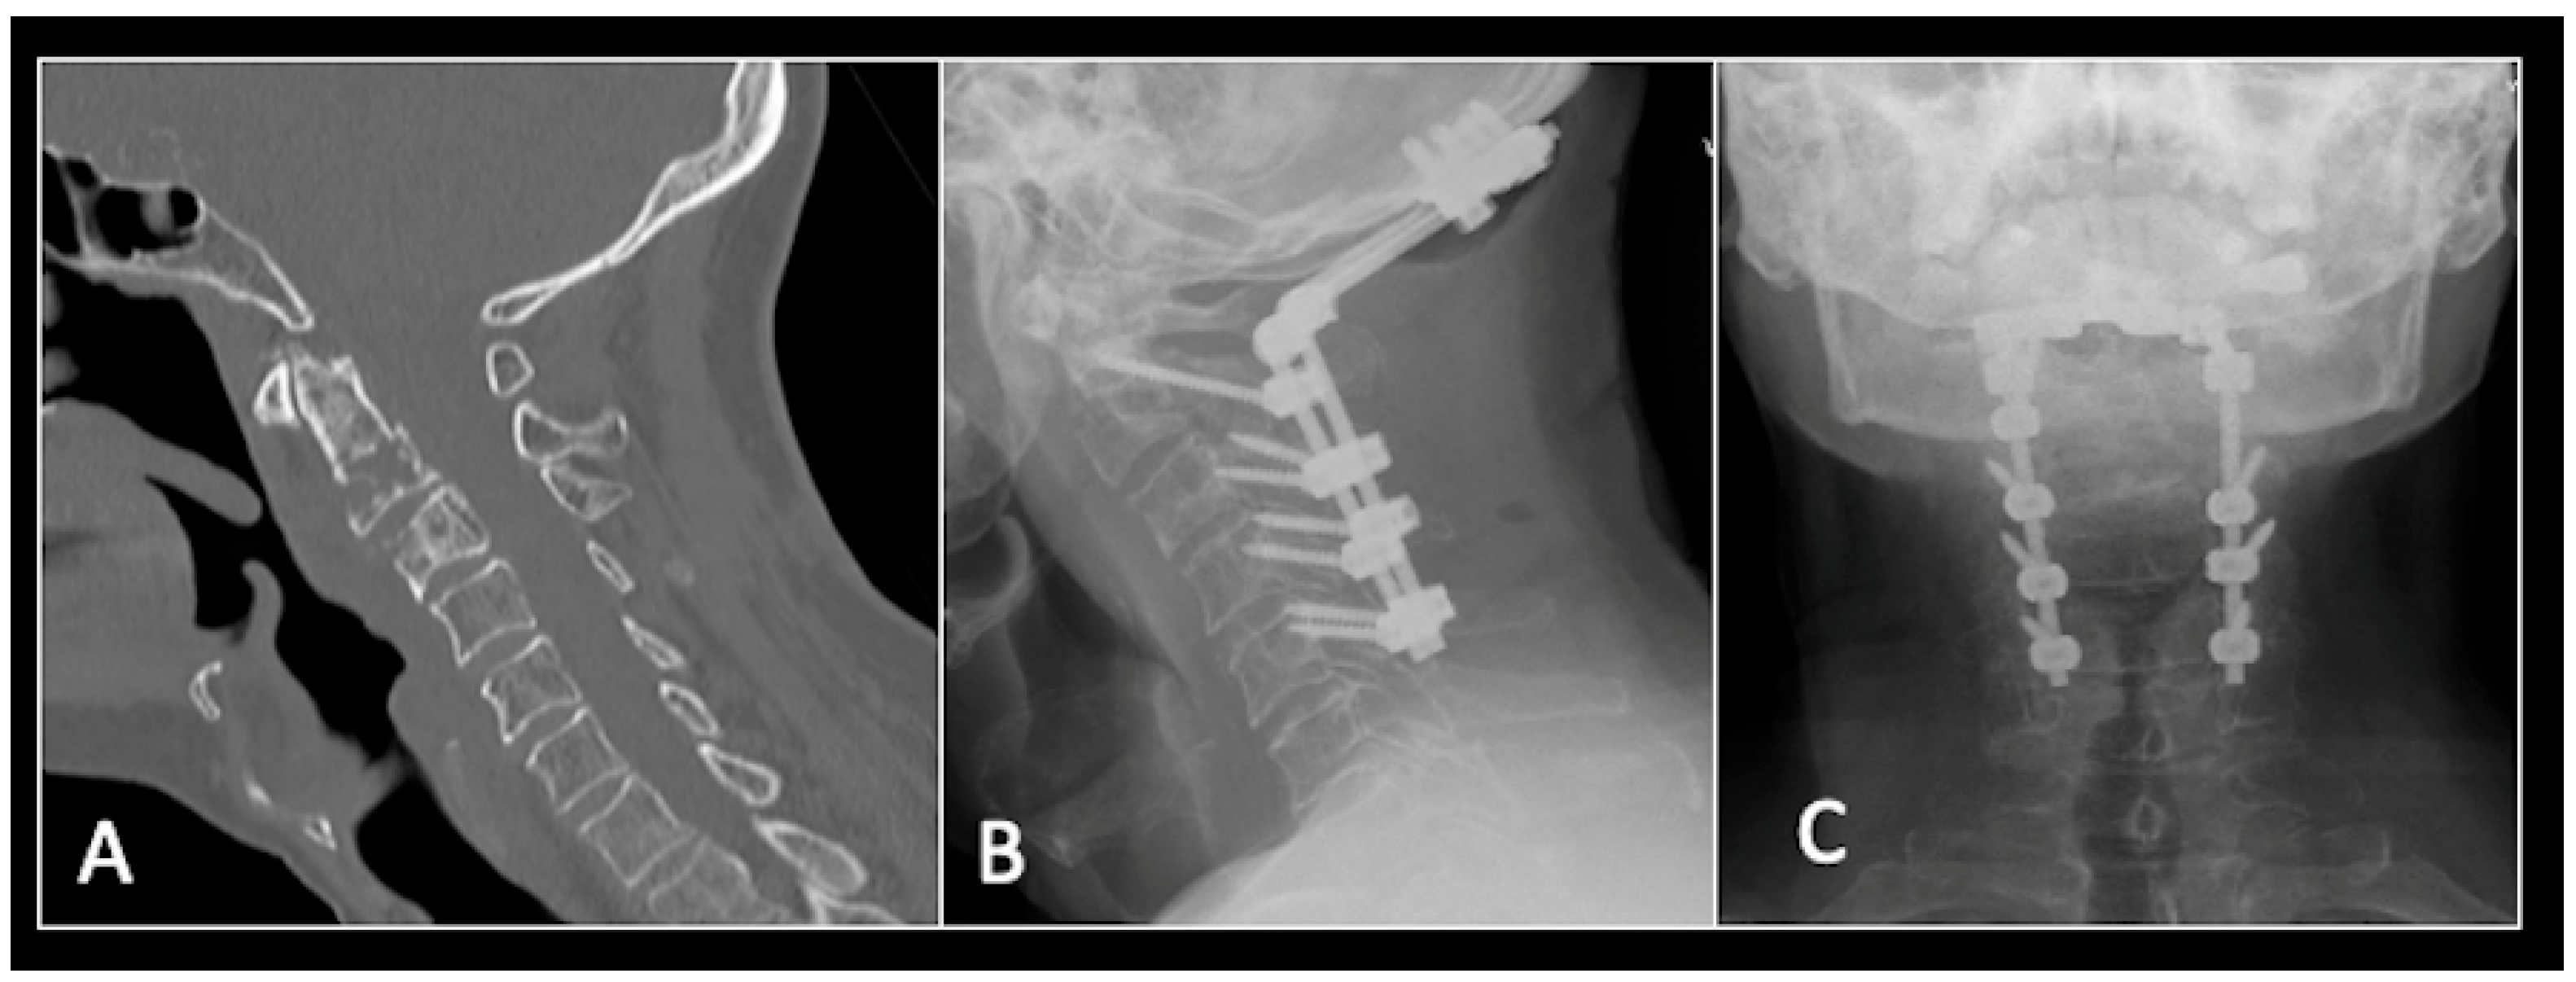

This 56-year-old lady was diagnosed with a biopsy-confirmed L2 chordoma (Figure 11). She underwent posterior decompressive separation surgery and instrumental stabilisation T12-L4 using carbon-based implants (Figure 12). Surveillance imaging at 6 months and 12 months post-separation did not show any progression of residual tumour disease (Figure 13 and Figure 14).

Figure 12.

(A) demonstrates an anteroposterior view, and (B) illustrates a lateral standing radiograph of the lumbosacral spine demonstrating carbon-based posterior instrumentation.